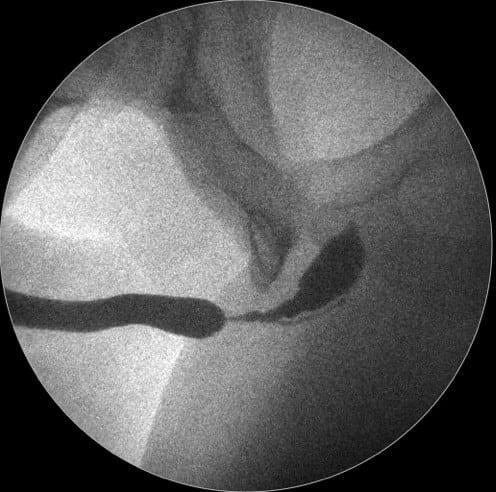

Dr. Marcel Rad – Când evaluăm strictura de uretră ce vedem? Vedem un canal, vedem în uretrografie o zonă de gâtuire, de stenozare a canalului, dar nu vedem şi nu putem să ne dăm seama, indiferent de cât ne chinuim să evaluăm cu ecografie, cu RMN, nu putem să evaluăm corect zona de fibroză, zona de ţesut cicatricial.